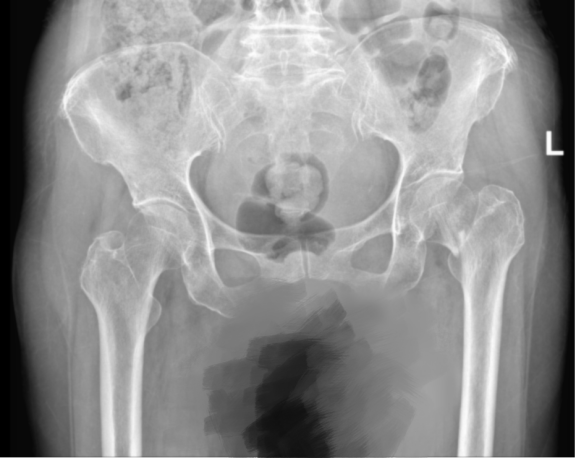

术前 术后

76岁的TAY女士在游览时不慎跌倒,经急诊检查确诊为左侧股骨颈骨折。面对突如其来的伤痛与陌生的医疗环境,她表示在国内接受手术充满担忧:“我曾听说不同国家的医疗标准存在差异,手术效果和术后康复能否达到国际水平。”同时,TAY女士的保险公司得知情况后,迅速安排新加坡专员跟其对接,准备派遣医疗救援直升机接患者到澳门/香港国际机场,转商务民航紧急回国治疗。但因骨折疼痛剧烈、长途转运风险高而陷入两难。

经过周密的术前评估,手术仅用30分钟便顺利完成。术中,出血量不足50ml。术后第二天,TAY女士即在陪护下借助助行器实现自主行走。她惊叹道:“想不到中国的医疗水平发展已如此日新月异。”